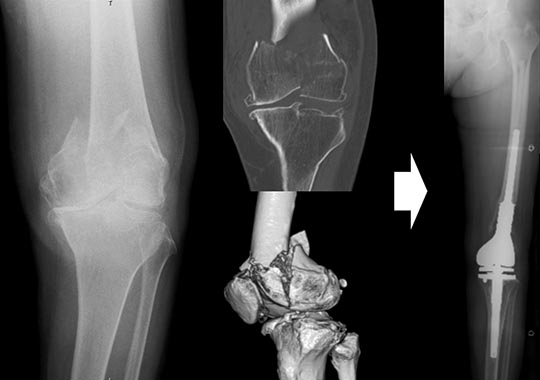

- 高齢者で、骨折部の粉砕が強く、骨折部を治してもうまく固定ができないような方や、もともと重度の変形性膝関節症を合併する方では、早期の荷重歩行を目的に最初から人工膝関節置換術を選択する場合があります(図4)。

図4.80歳の右大腿骨遠位部骨折ですが、もともと変形性膝関節症を合併しており、かつ関節内の粉砕骨折も認めるため、最初から人工膝関節全置換術を選択しました。